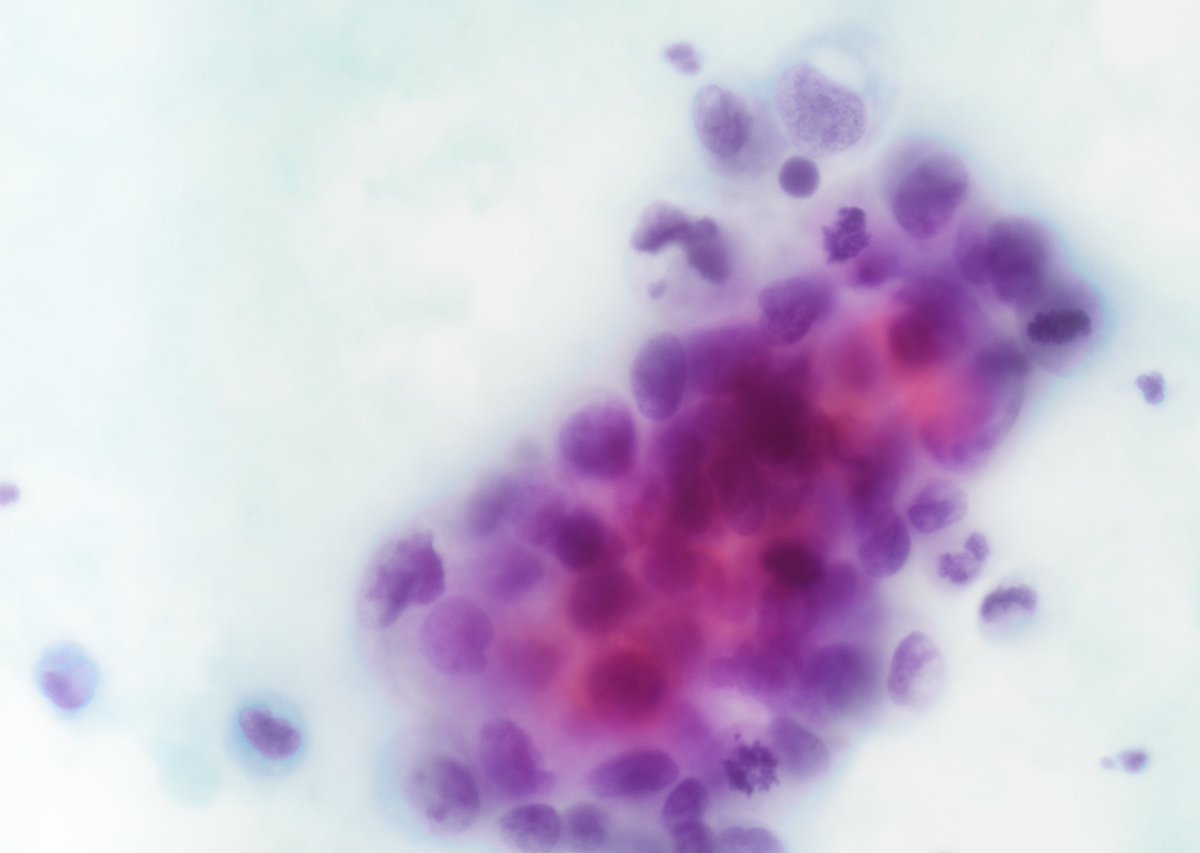

65yo F with 1.3cm LLL lung nodule. Core biopsy of the mass was performed. #pathology #pathtwitter #pulmpath #pathboards Jui Choudhuri Ridin Balakrishnan, MD Pembe Oltulu, MD Celina Stayerman MD Vish Killari MD MPH Brian Cox, MD, MAS Rana Saleh, MD Adam L. Booth, MD